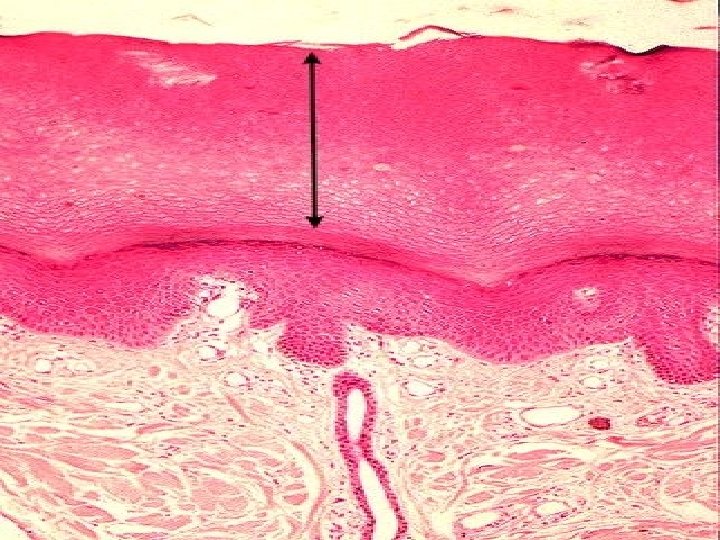

TYPES OF SKIN • Thin skin – covers all parts of the body except for the palms and palmar surfaces of the digits and toes. – lacks epidermal ridges – has a sparser distribution of sensory receptors than thick skin. • Thick skin (0. 6 to 4. 5 mm) – covers the palms, palmar surfaces of the digits, and soles – features a stratum lucidum and thick epidermal ridges – lacks hair follicles, arrector pili muscles, and sebaceous glands, and has more sweat glands than thin skin.

Specific Layer of the Skin Epidermis: • Composed of keratinized stratified squamous epithelium Dermis: • Papillary region composed of areolar tissue • Reticular region composed of dense irregular connective tissue Hypodermis: • Composed of areolar tissue with abundant adipocytes

Specific Layers of the Epidermis Stratum Basale: • Mitotic layer, continuously replaces epidermal cells, turnover rate between 25 to 50 days Stratum Spinosum: • Cells are pushed upward and flatten out Stratum Granulosum: • Cells contain granules of Keratin

Specific Layer of the Epidermis Stratum Lucidum: • Observed only in nonhairy or thick skin. Several layers of dead cells with indistinct boundaries Stratum Corneum: • Composed of 25 or more layers of dead squamous cells still joined by desmosomes. Eventually desmosomes break and cells flake off in a process called desquamation